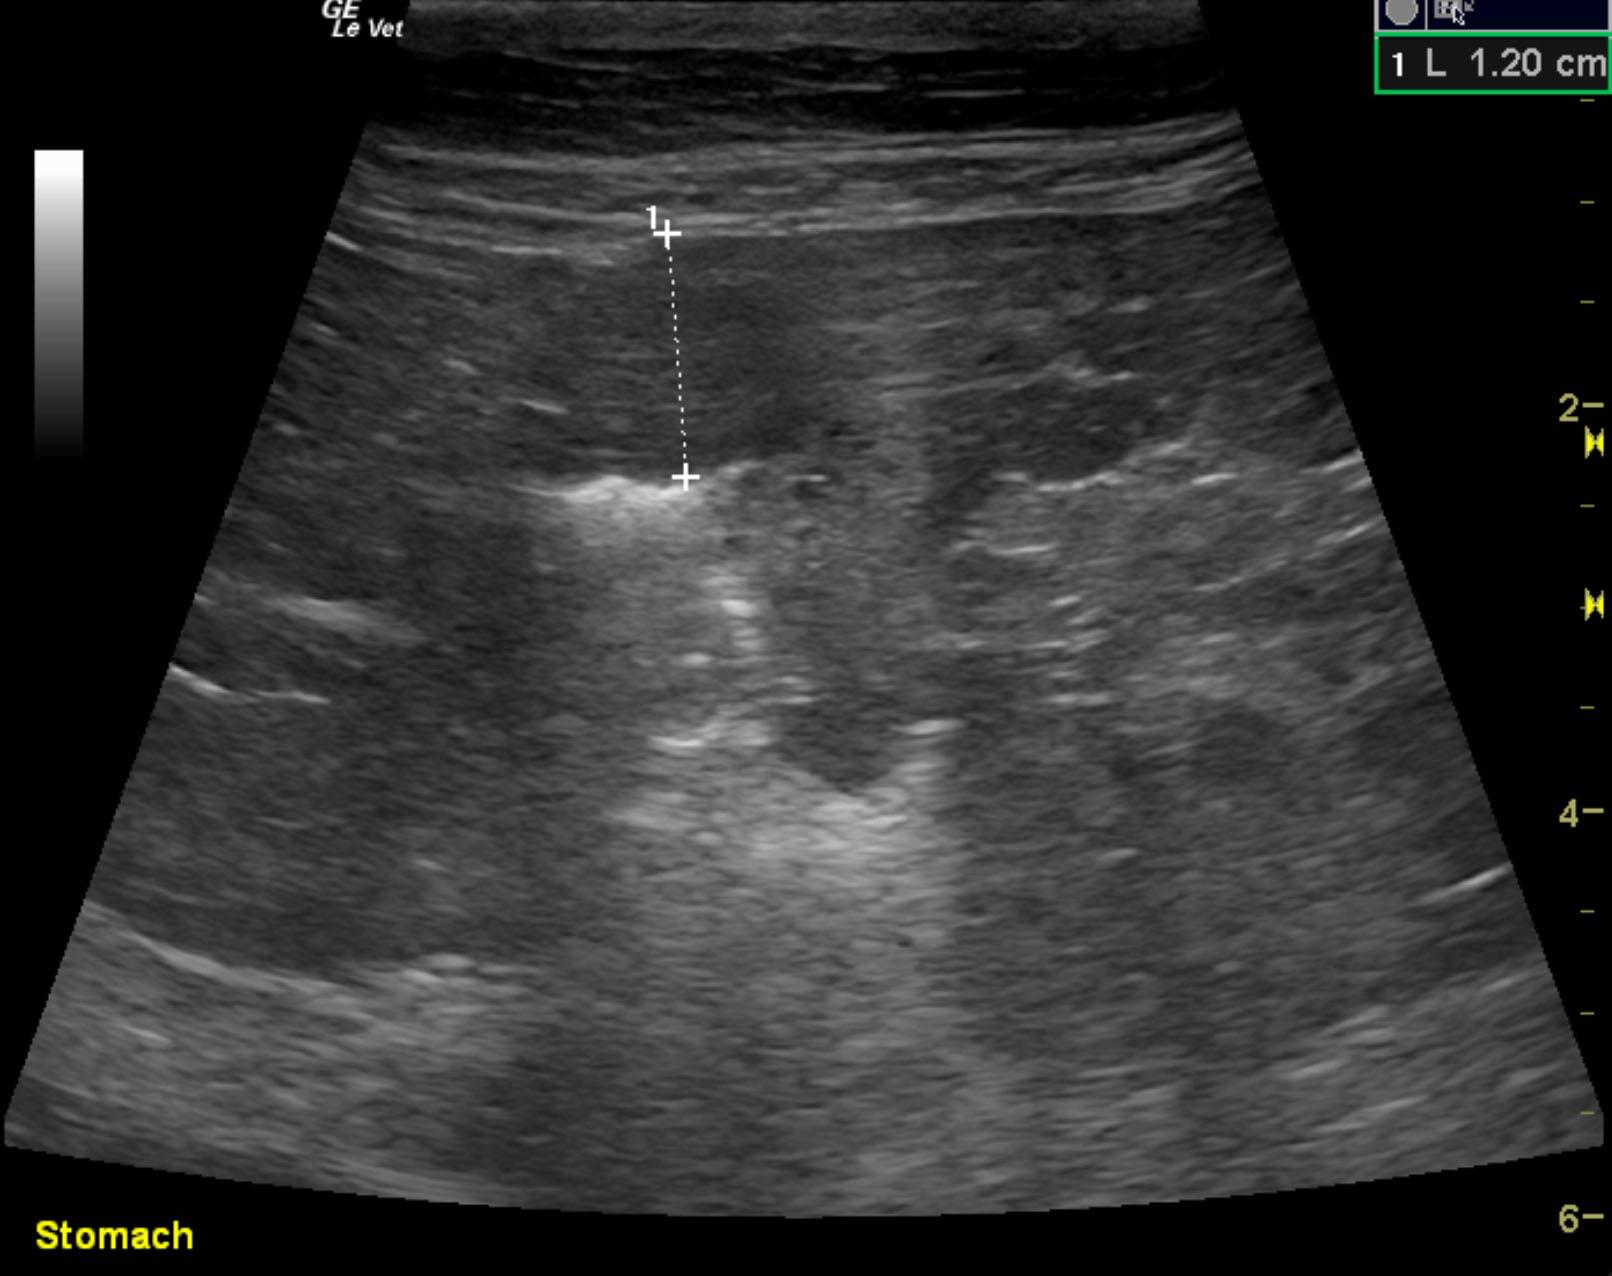

The patient is a feline DSH, NM, 14 years. The patient was hospitalized last week for pancreatitis, but specfPL remains elevated and has increased. The patient is now anemic and albumin is 2.2.